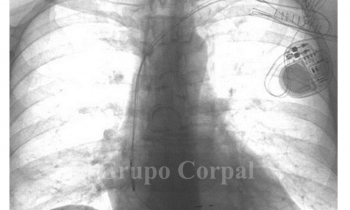

Estimulación cardiaca con sincronía

Blog Cardiológico

por Grupo Corpal | 23 Sep, 2021 | Blog Cardiológico, Imagen del mes

Estimulación cardiaca con sincronía en paciente con bloqueo aurículo-ventricular completo La estimulación cardiaca supone una herramienta muy útil que, en ocasiones, resulta vital. Trata las alteraciones del ritmo que...

by Grupo Corpal 23 Sep, 2021